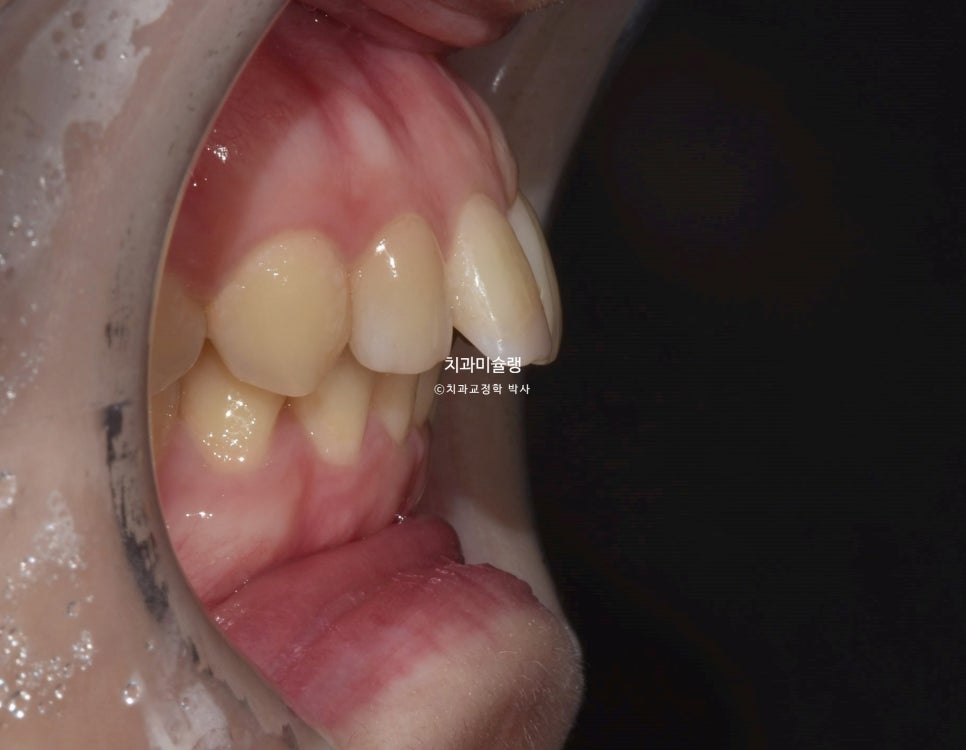

앞니뿐 아니라 어금니 교합관계가 2급입니다.

악궁이 좁고 뾰족합니다.

한쪽 사랑니가 깨끗하게 잘 나와있습니다. 반대쪽 사랑니도 곧 내려오겠죠.